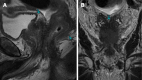

Case summary: Three patients with secondary RLP due to prostatic adenocarcinoma presented with varied clinical features. The first patient, a 76-year-old man with advanced prostate cancer, had rectal pain and incontinence. MRI showed diffuse prostatic invasion and significant rectal wall thickening with a characteristic "target sign" pattern. The second, a 57-year-old asymptomatic man with elevated prostate-specific antigen levels and a history of prostate cancer exhibited rectoprostatic angle involvement and rectal wall thickening on MRI, with positron emission tomography/computed tomography PSMA confirming the prostatic origin of the metastatic spread. The third patient, an 80-year-old post-radical prostatectomy, presented with refractory constipation. MRI revealed a neoplastic mass infiltrating the rectal wall. In all cases, MRI consistently showed stratified thickening, concentric signal changes, restricted diffusion, and contrast enhancement, which were essential for diagnosing secondary RLP. Biopsies confirmed the prostatic origin of the neoplastic involvement in the rectum.